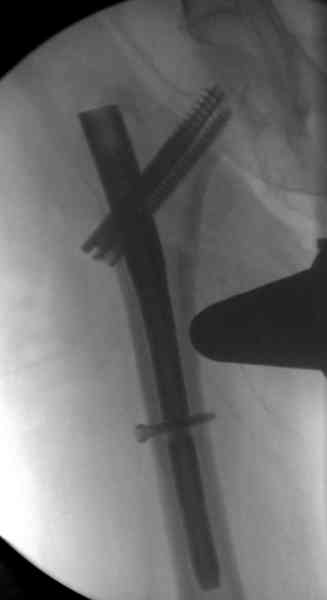

Александр, поздравляю от души, отличная работа, вообще-то и у меня тоже были опасения по поводу латеральной стенки. Идеальное показаниt к применению импланта закрытым методом при таких переломах, когда болт замыкается в штифте, конструкции придается угловая жесткость, примерно как в Blade Plate.

Здесь сканнированные снимки импланта и операционные снимки больной.